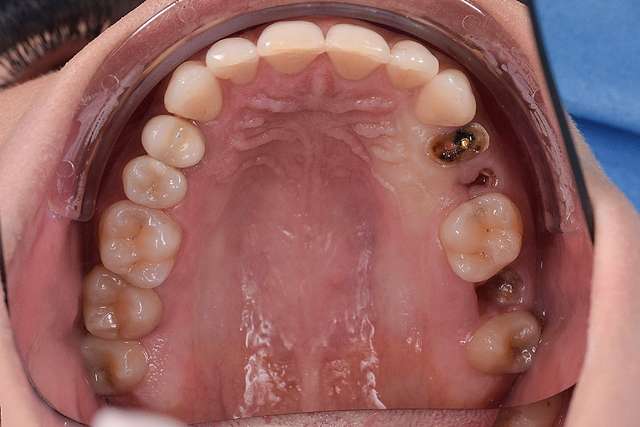

Dental implants are treatments designed for teeth that we can no longer save. Dental implants rely on the principle of osseointegration, or in other words, on the implant being integrated in the bone. For a long period of time, this was the main objective of the industry. Osseointegration, placing implants in relation to bone. Today , we know that osseointegration is extremely predictable and we focus on key elements that can make the difference in the quality of the end result.

Guided surgery, for one, facilitates an ideal pre-planned position, in relation to available bone, and even more important, in relation to the future implant supported crown. Guided surgery translates into increased precision, which means safer surgeries, reduced surgery time, and reduced trauma. Also the focus of these types of treatments is shifted towards tissue reconstruction, which on the long run, has a far greater impact esthetically and biologically. Tissue stability means implant longevity. This case is a relevant example for this type of approach towards implant dentistry.